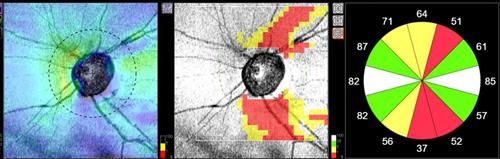

Glaukooma on näköhermosairaus, joka lähtee yksinkertaistettuna katkomaan viestiyhteyttä silmänpohjan aistisolujen ja näköaivokuoren väliltä. Mikäli glaukooman hoito laiminlyödään, se johtaa ensin näkökenttäpuutoksiin näkökentän reuna-alueilla ja pitkällä aikavälillä hoitamaton glaukooma sokeuttaa. Glaukooman ensimmäiset merkit havaitaan yleensä silmämikroskoopilla näköhermonpäätä tutkiessa asiaan kouluttautuneen optometristin tai silmätautienerikoislääkärin toimesta. Glaukooma on myös monesti perinnöllinen sairaus. Tämän vuoksi silmien säännöllinen tutkiminen, varsinkin yli 40-vuotiailla on erittäin tärkeää. Silmätautienerikoislääkäri tekee aina lopullisen diagnoosin ja määrittää tarvittavat hoitokeinot.

Glaukoomaa pystytään havaitsemaan esimerkiksi näköhermonpään OCT-kuvauksella